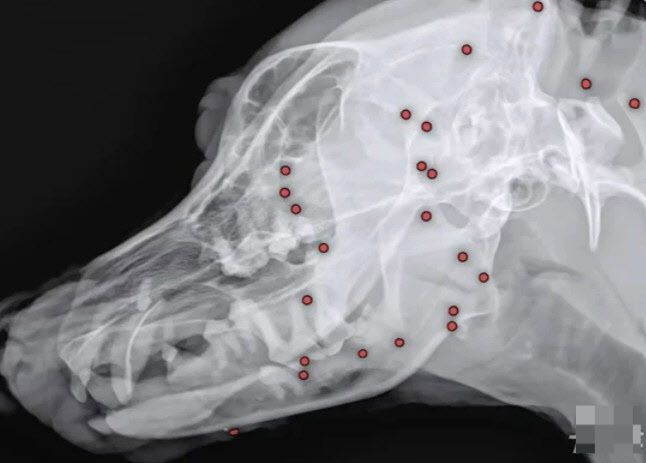

구조 당시 겉으로 보기에 드러나지 않던 산탄총 총알들은 원인을 알 수 없는 이유로 백구 온 몸에 박혀 있었고, 동물병원에선 엑스레이, CT(컴퓨터단층촬영) 등 정밀검사에 들어갔다.

산탄총 파편 제거 수술은 총 3시간 동안 진행됐다. 맨눈으로 탄알을 다 확인할 수 없어서 투시기를 이용해 일일이 수술해야 했다고.

안 원장은 “탄알을 한 번에 다 제거하기는 현실적으로 어려워 백구의 얼굴을 위주로 최대한 많이 제거하는 방향을 선택했다”며 총 26개의 파편을 제거했다고 밝혔다.

수술 후 백구의 얼굴 부분에서만 총알 26개가 제거됐다. 백구의 엑스레이 사진. (사진=VIP동물동물의료센터) |